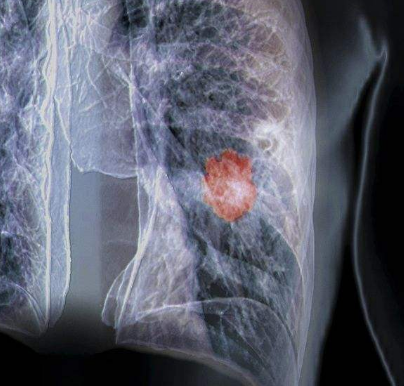

肺癌是发病率较高的恶性肿瘤,其恶性程度是很高的,肺癌在药物化疗时,会出现耐药性,这是一个治疗上的难题,较近,美国科学工作者,通过对表皮生长因子受体(EGFR)突变的非小细胞肺癌(NSCLC)患者进行研究,鉴别出了一种特殊酶类与癌症形成及对治疗方法耐受性直接相关,研究人员认为,现有的两种治疗方法对这种致死性常见肺癌或许具有一定的治效果果,但这种肺癌常常会在患者治疗一年内发生复发。

研究者揭示了NSCLC肿瘤中所发现的名为PKCδ的蛋白激酶C和EGFR酪氨酸激酶抑制剂(TKIs)标准化治疗方法之间的特殊关系,基于对小鼠和人类组织样本进行研究,这种关联或许就能帮助PKCδ降低TKIs预防癌症形成的能力。目前在美国每年大约会有16万人会被诊断为NSCLC,而且大约有1.5万人会出现携带EGFR突变的癌症转移疾病。

EGFR属于受体酪氨酸激酶(RTKs)家族的蛋白,其常常会在NSCLC中发生频繁突变,从而诱发细胞损伤,包括增强细胞生长、肿瘤形成和转移等,TKIs能够干扰EGFR的细胞信号并抑制肿瘤的发育;然而在治疗肿瘤时较终会因多种机制让肿瘤对治疗方法产生耐受性,其中一种机制就是肿瘤的异质性耐药性,其包括EGFR的额外突变和其它RTKs的过量表达等。